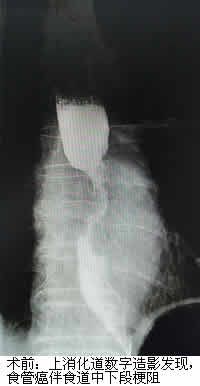

郑老伯今年已81岁高龄,因“进行性吞咽困难1月余”就诊当地医院,诊断结果为晚期食管癌。由于年纪大不宜手术,郑老伯一年内行多次放化疗后仍出现食管肿物进行性增大,原来吃面食现在只能喝水,甚是痛苦。经打听,他们了解到福建医科大学附属第一医院介入科通过一种无创的食道支架植入术可以姑息性治疗晚期食管癌,遂转诊我院。在充分了解病情及完善相关检查后,我院介入科治疗团队为郑老伯进行了这种无创手术,手术很顺利,疗效显著。术后第二天医生告诉老伯可以继续吃面食了,郑老伯非常开心,其家属也相当满意,十分感谢我院陈一平、陈仲武两位专家及其团队。

陈一平、陈仲武副主任医师介绍说,食管癌的最大问题是因食道阻塞而患者无法进食,常规上会以肠或胃造瘘的方式解决患者营养或者排便的问题。但胃造瘘仍无法让患者经口进食,而食道支架,可用以撑开肿瘤阻塞的食道,满足患者经口进食的口欲,使患者的营养得到保障,此外,该手术具有疼痛轻、并发症少等优点,对患者也是巨大的心理安慰。食道支架植入术是晚期食管癌患者实现食道再通的一种有效治疗手段。